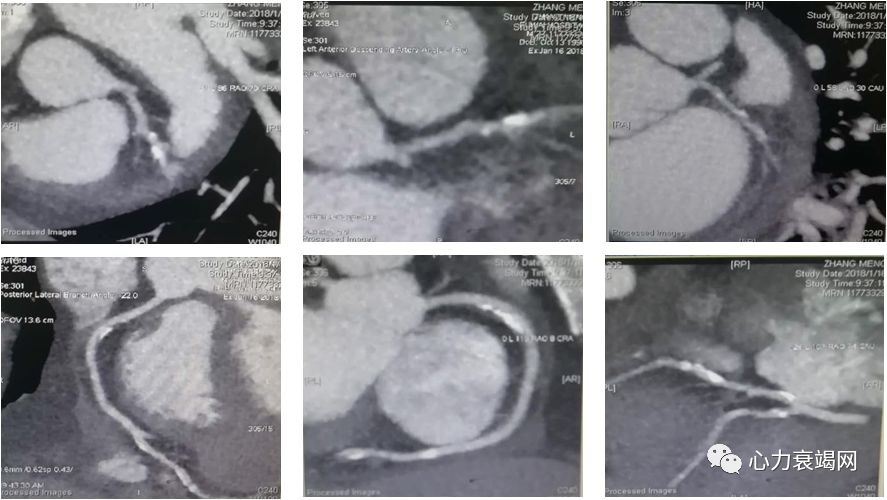

➤ 冠脉动脉成像

冠状动脉平扫:左、右冠状动脉可见钙化,积分698分;冠状动脉呈右优势型;前降支中远段管腔极细,考虑闭塞;回旋支中远段及钝缘支细小,间断显影;右冠状动脉未见有意义狭窄。

左房室增大;心包少量积液。

双肺下叶后基底段、外基底段少量渗出,考虑与心功能不全有关。